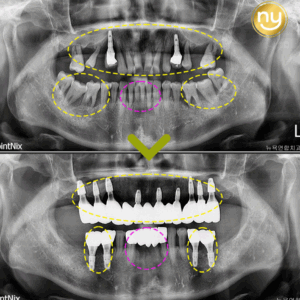

처음 본원에 내원하셔서 찍은 파노라마 사진입니다.

전체적으로 잇몸뼈의 소실이 심하고

하악의 브릿지와 크라운을 수복한 치아들도

염증이 발생되어 있는 것을 보실 수 있는데요.

염증과 치주 질환으로 인해 치아 흔들림이 심해 상악 송곳니 2개와

작은 어금니 1개를 제외하고는 살릴 수 있는 치아가 없어서

상악 구치부의 경우 오른쪽 3개, 왼쪽 2개를 식립하여

어금니의 역할을 수행할 수 있도록 제작해드렸는데요.

상악의 경우 잇몸뼈가 많이 소실되어 있는 상태라

길이가 짧은 임플란트를 사용하여 식립하였고

별도의 뼈이식 없이 임플란트 식립을 진행하였습니다.

하악에는 전치부 2개, 구치부 각 오른쪽 4개,

왼쪽 3개의 임플란트 식립으로 총 12개 치아의 기능을 회복하였습니다.

하악 오른쪽 뒤 큰 어금니와 왼쪽 송곳니 쪽에는 염증이 심했던 상태라

임플란트의 식립이 어려워, 큰 어금니 1개를 제외하고

위아래 모두 12개씩 총 24개의 치아 기능을 회복하였습니다.

전체적인 기간은 1년이 걸렸으며,